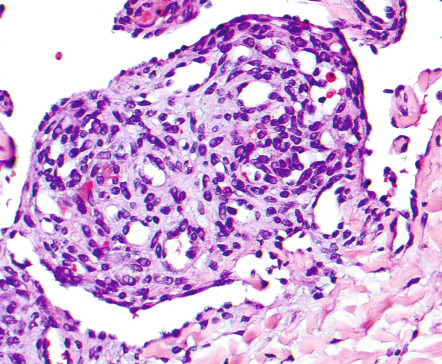

Pathology

Most of the angiomas seen in patients with POEMS syndrome are found upon histologic examination to be consistent with common cherry angiomas, with numerous dilated dermal capillaries lined by flattened endothelial cells (see above). Only a few demonstrate the distinctive features of glomeruloid hemangioma. These consist of dilated dermal vessels filled by small, well-formed capillary loops that lead to structures reminiscent of renal glomeruli ( Fig. 114.15 ).

The capillaries comprising these glomeruloid formations are lined by flat endothelial cells surrounded by an outer layer of pericytes and are separated by a scant stroma containing large cells with lightly eosinophilic cytoplasm and multiple eosinophilic globules. The latter are PAS-positive, diastase-resistant, and immunopositive for polytypic immunoglobulin, presumably derived from the associated paraprotein . Of note, these interstitial, immunoglobulin-containing cells are of endothelial derivation. Lastly, since many POEMS syndrome patients have both cherry angiomas and glomeruloid hemangiomas, and the cherry angiomas may display focal glomeruloid formation, it is likely that these two histologic subsets reflect different stages of the same process .